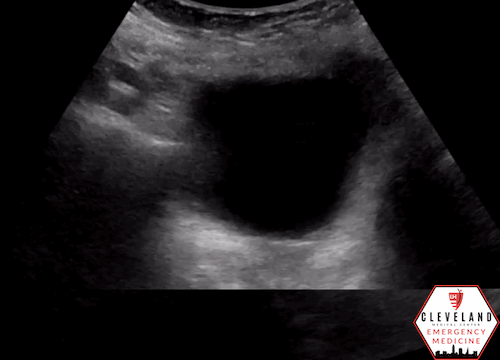

Renal POCUS was performed to evaluate for hydronephrosis and showed the following:

POCUS findings:

There is hydronephrosis of the left kidney. The right kidney is normal-appearing. Bladder views incidentally revealed a large complex, fluid-containing lesion in the pelvis (color doppler negative).